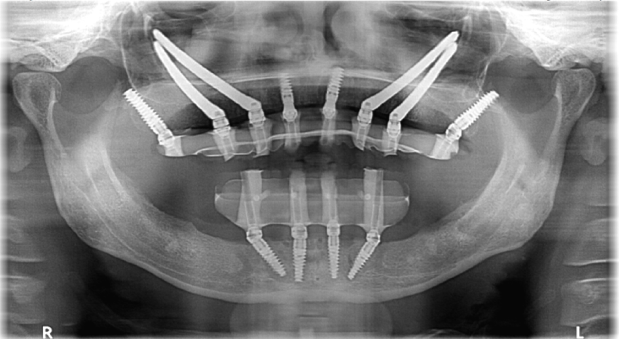

Advances In Dental Implantology